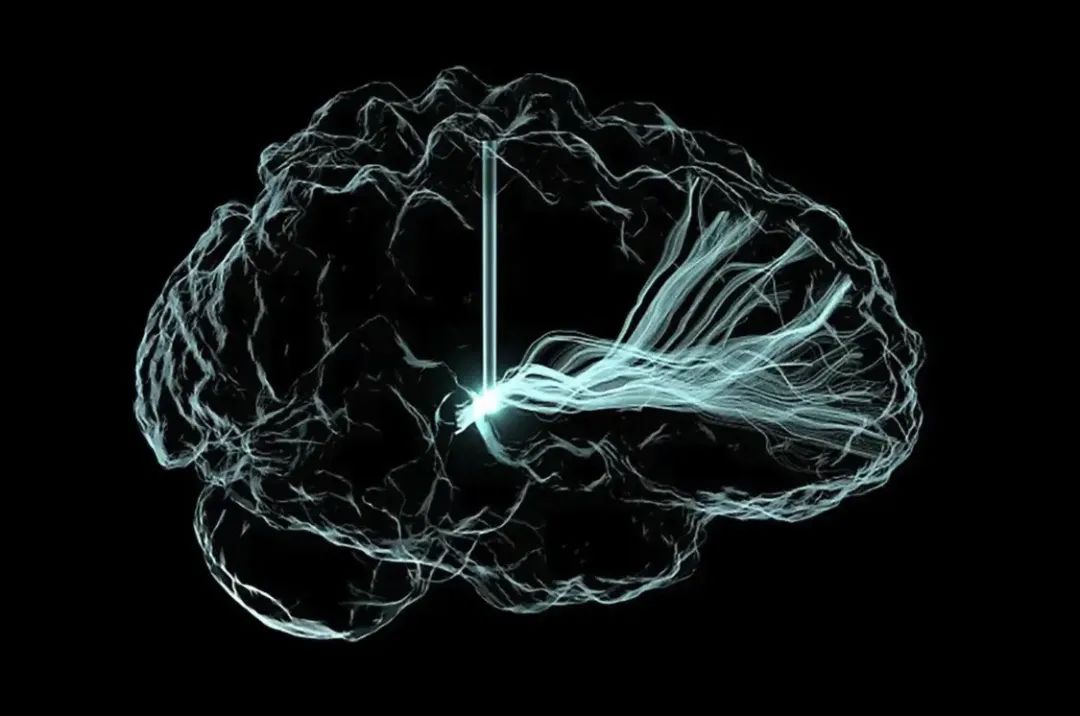

他指出,绝大多数疾病或大脑问题,都可以通过Neuralink的脑机接口来解决,“如果你把大脑想象成一台电脑,一块电路板或之类的东西,如果说,给你一块电路板,它有些短路,或者缺失一些应该存在的电路,如果包括一些不应该存在的电路,这些问题我们都能修复。”

Neuralink成立于2016年,这家公司的主要研究方向就是脑机接口,通过研发一种能够植入大脑的设备,来实现“人脑与机器交互”。公司成立之后获多轮融资,据外媒报道,早在2023年6月,Neuralink估值已超过50亿美元。